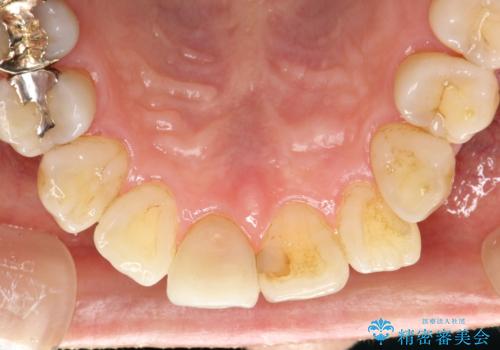

- 約2~3か月ごとに、定期的メンテナンスをしている方です。毎日紅茶をたくさん飲むとのことでステインを気にされ、クリーニング希望で来院されました。

専門的な機械や材料を使用し、60分コースのPMTCクリーニングで、全体的な歯石や着色の除去を行いました。